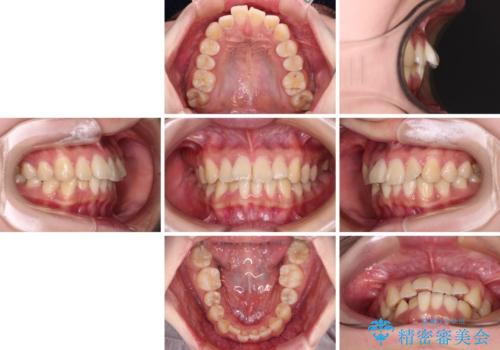

- 前歯の捻れを気にして来院された患者様です。

上顎前歯が捻れて前方に飛び出しており、下顎前歯もそれに沿うようにデコボコとなっていました。

IPR(歯と歯の間を削る処置)によりスペースを獲得して下顎前歯のデコボコを改善し、上顎前歯は下顎前歯と接する位置にまで引っ込めるように設定し、インビザラインにて矯正治療を行うこととしました。